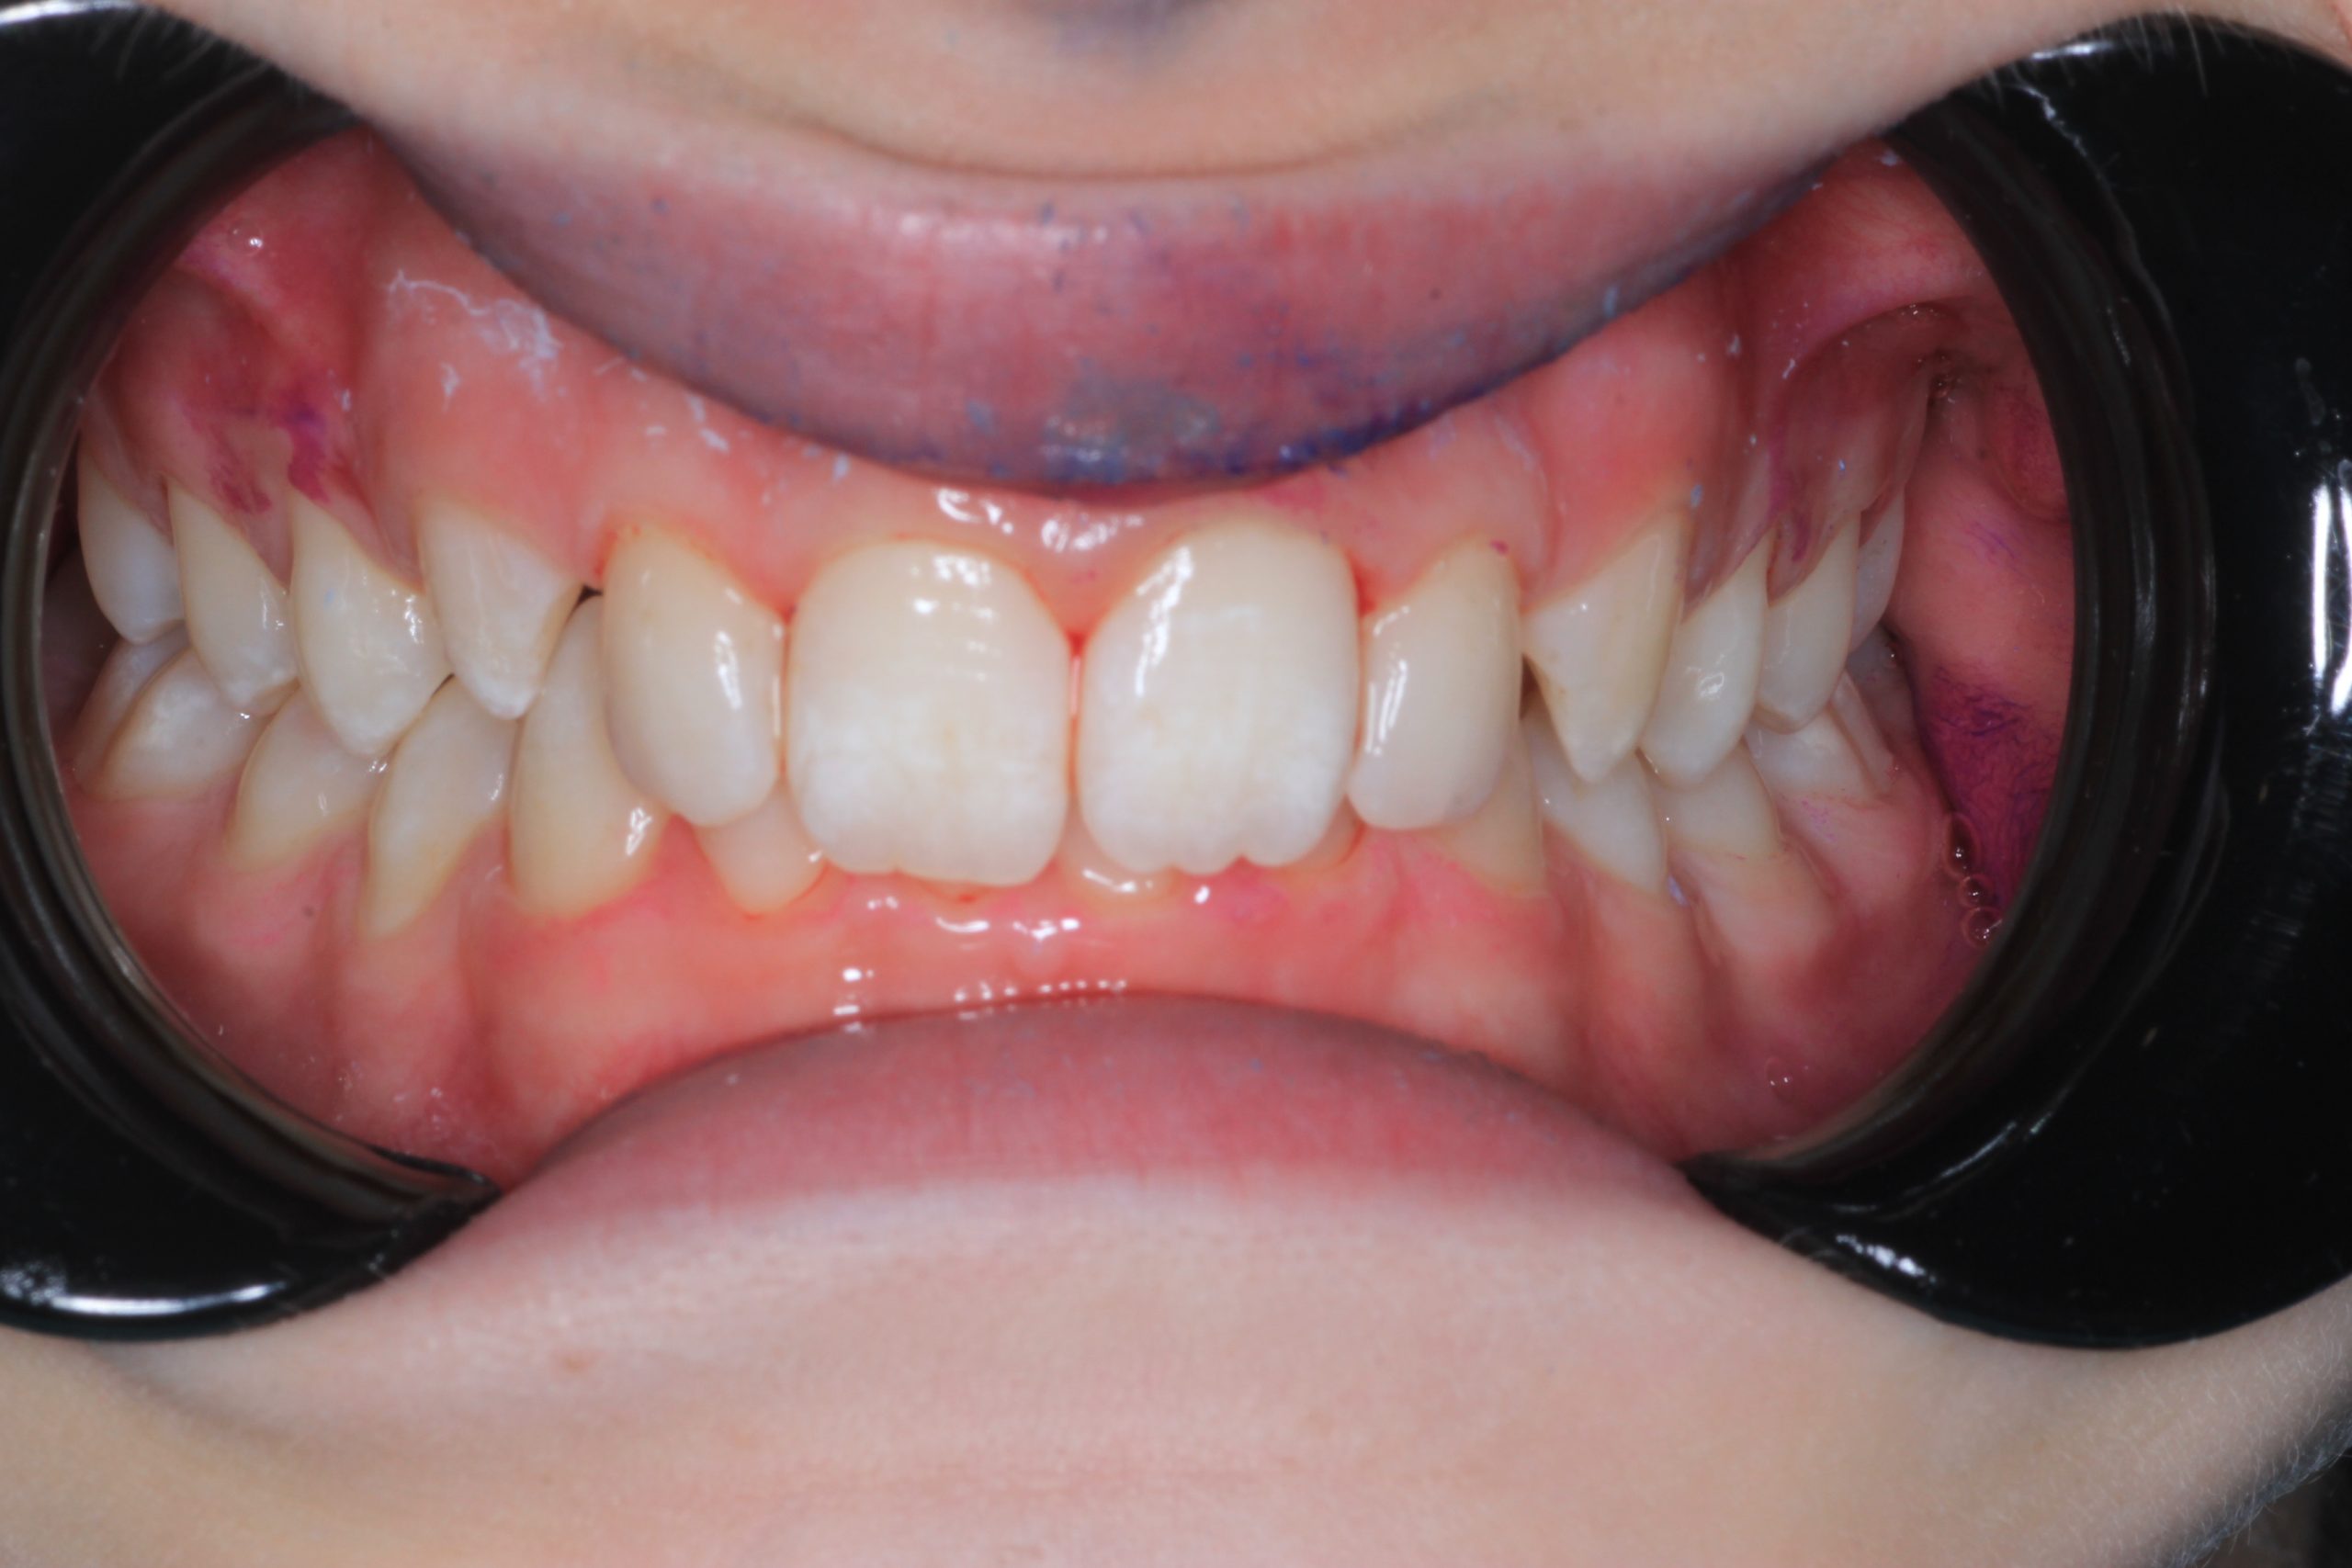

We examine the condition of teeth, gums, and bite. - Plaque Disclosure with Special Indicators

Areas that weren’t cleaned well appear purple. The darker the shade, the older the plaque. This helps both kids and parents understand where brushing needs to improve. - Brushing Training & Home Care Tools Selection

- We use plaque-disclosing agents, so both parents and children see which teeth were not cleaned properly.